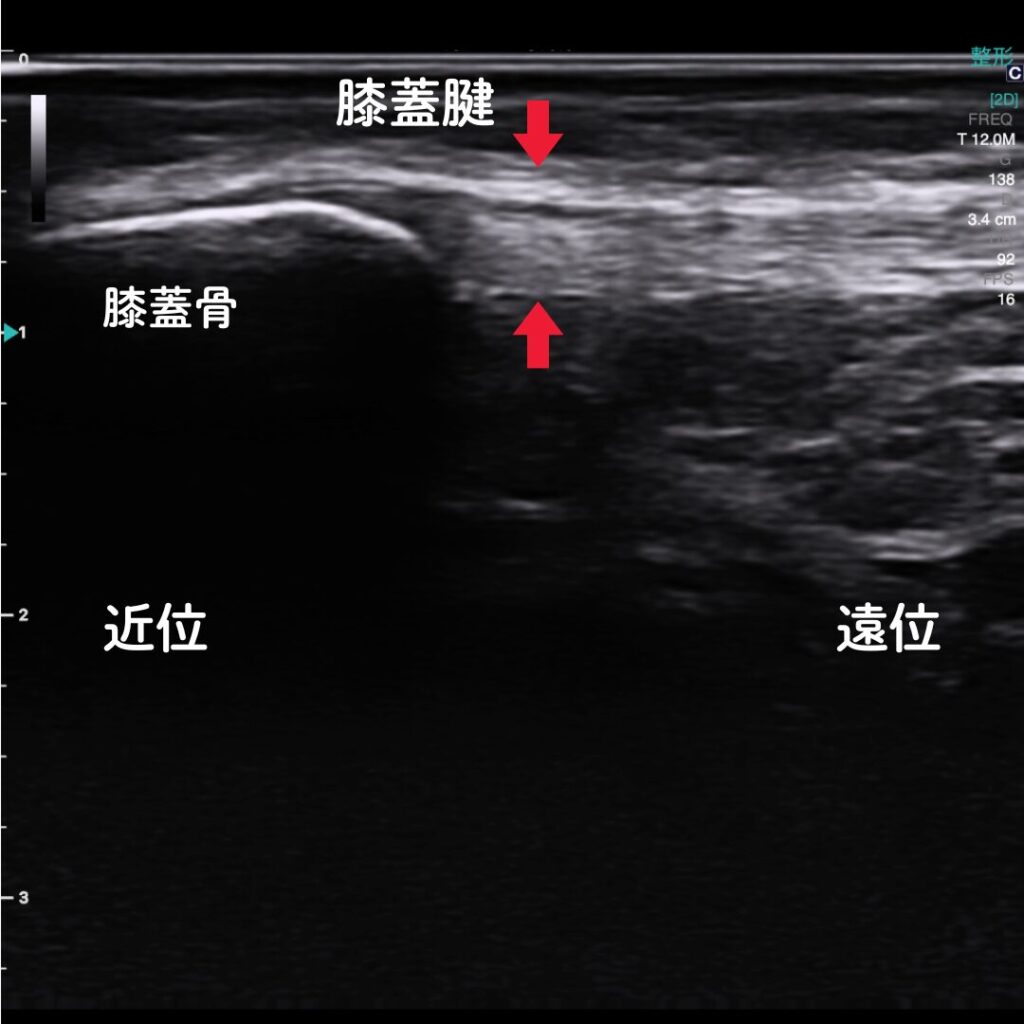

🔶エコー(超音波観察装置)で原因を“見える化”

エコー観察により、膝蓋腱の炎症や損傷の程度をリアルタイムで確認できます。

レントゲンでは写らない腱や軟部組織の状態を可視化し、痛みの原因を正確に特定します。

また腱付着部の骨異常も観察可能。